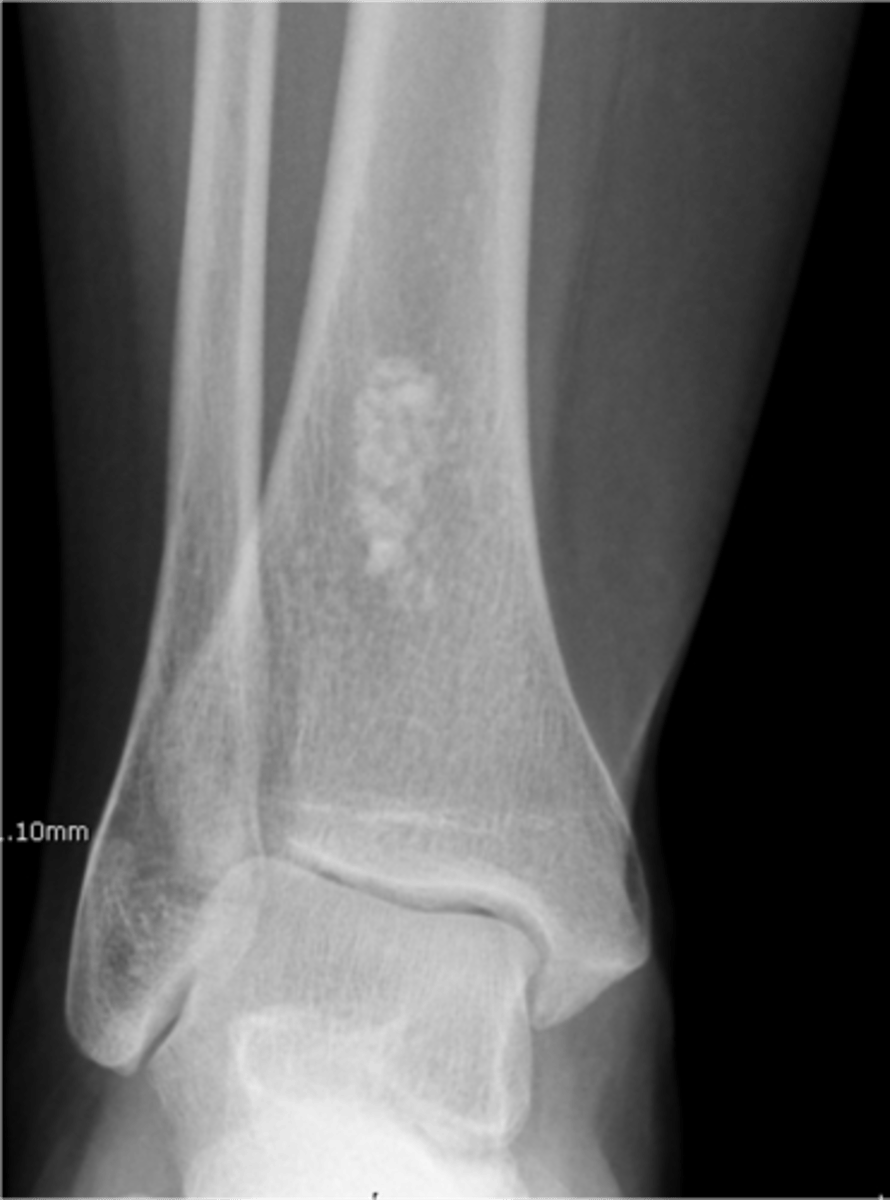

49

New cards

Matrix calcification

ID feature of solitary enchondroma

<p>ID feature of solitary enchondroma</p>

50

Endosteal scalloping